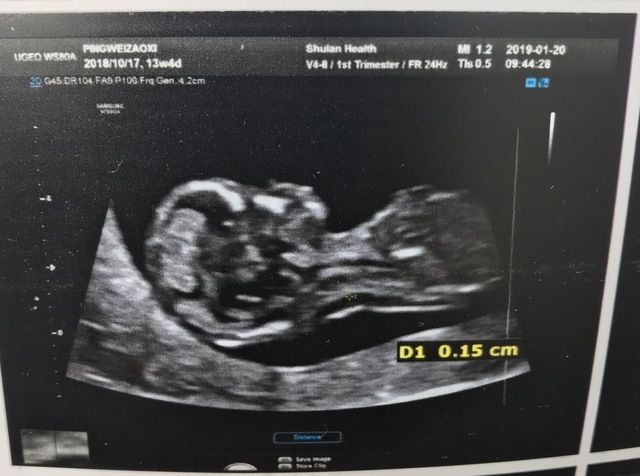

14週4日(14w4d・性別不明)|みさき831 さん(23歳)

エコー写真撮影時のエピソード:

13週のエコー写真では、初めて超音波エコーによって顔・首・体が見えて感動しました。人間らしい形を見ることで、赤ちゃんを妊娠している実感が湧きました。生理不順だった為、赤ちゃんは少し小さいようです。これから、しっかり栄養を摂って赤ちゃんに大きくなってもらいたいです。

体調の変化は、これまで物をあまり食べられなかったのが、食べられるようになり、2時間おきにお腹が空くようになり困っています。